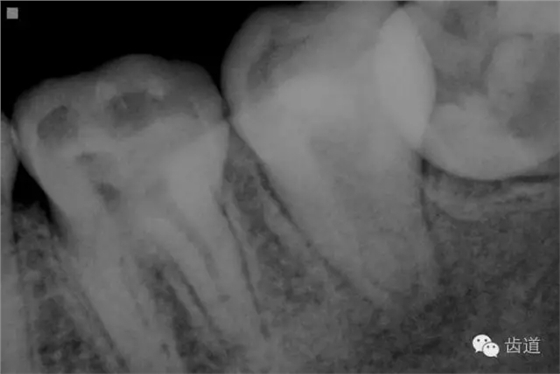

2. 術(shù)前X片

可見(jiàn)37根管影像清晰,根中上三分之二粗大,根尖三分一分為近遠(yuǎn)中兩根管,形態(tài)均呈弧形,根尖周膜連續(xù)性中斷,根尖周透射影明顯